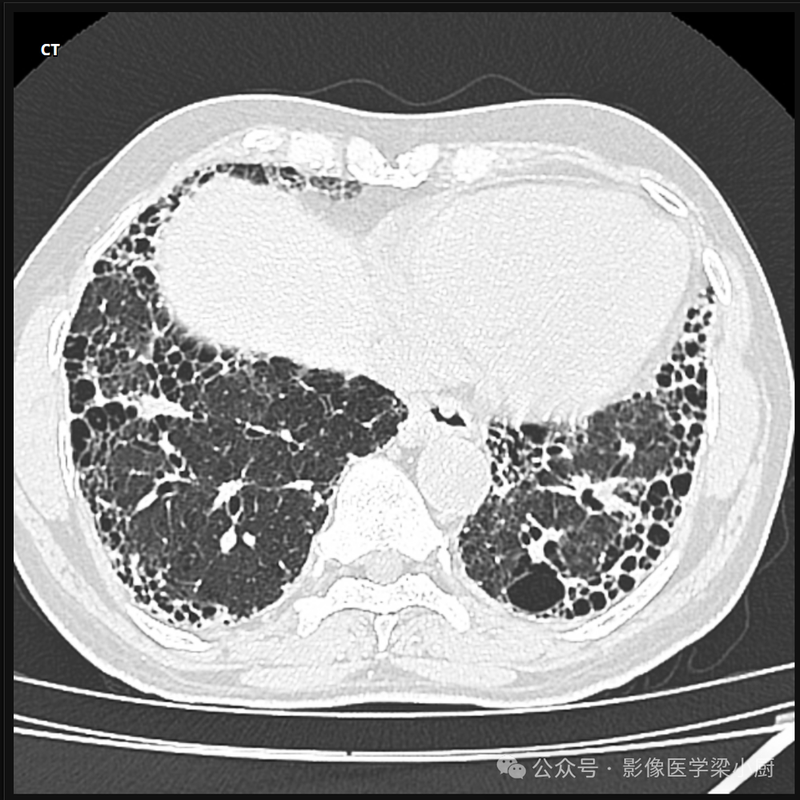

CT:

可见两侧肺野弥漫分布的网状影,以下肺野明显。HRCT可见小叶间隔及叶间胸膜增厚。有时,两肺可见多发弥漫分布的小片状或结节状影,边缘清楚或模糊。有时可见小叶肺气肿或肺不张征象。在急性间质性肺炎早期阶段,由于肺泡腔内炎症细胞浸润伴少量渗出液,肺泡内尚有一定的气体,可见磨玻璃样密度影。肺门和气管旁淋巴结可肿大。